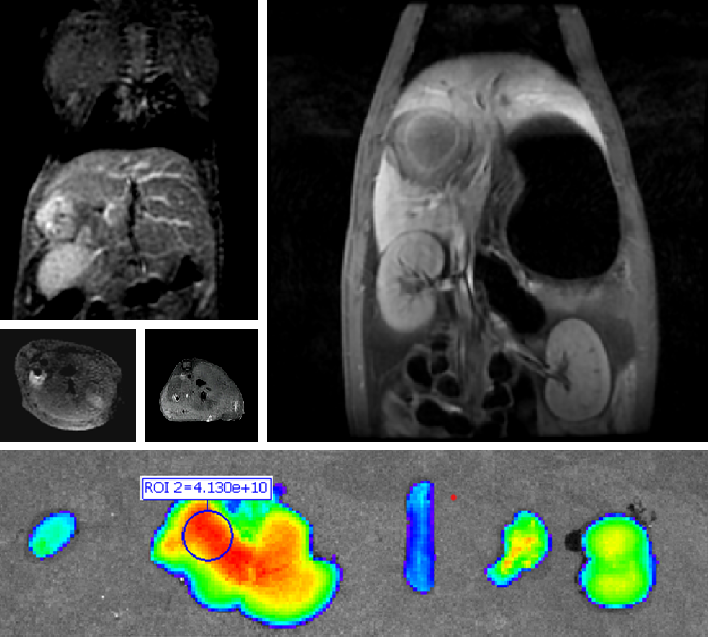

普利制药自主研发双模态造影剂PL002,首次提出通过整合磁共振技术,弥补现有荧光染料假阳性率高、透射深度有限等的短板,进而提升手术的精确性,降低手术过程中的风险,是全球首个获批临床试验的荧光/磁共振双模态造影剂,目前也已经获得美国FDA临床试验批件。

图片